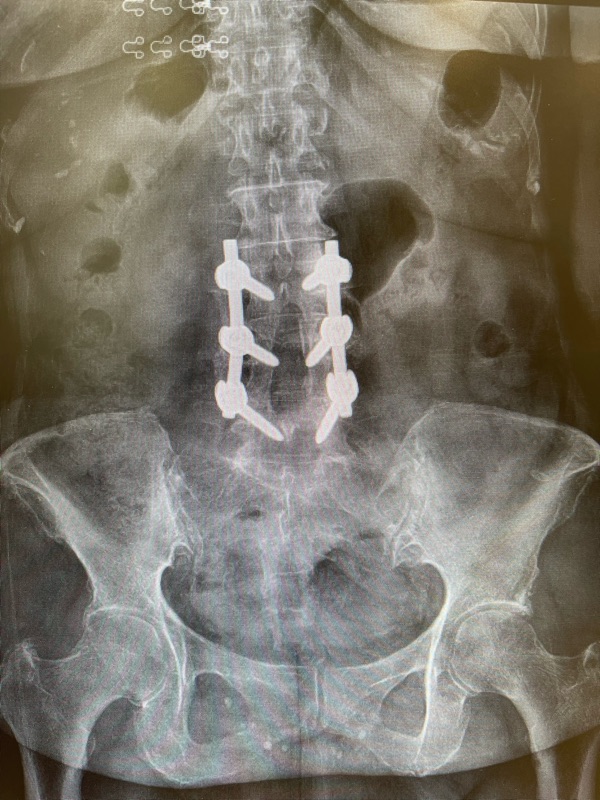

กรณีตัวอย่างนี้เป็นของ ผู้หญิงอายุ 67 ปี ที่ผ่าตัดใส่เหล็กดามกระดูกสันหลังมา 3 ปี แต่ยังมีอาการ

✔ 3) X-ray หลังยืน – ก้ม–เงย

เพื่อดูความมั่นคงของเหล็กดามและกระดูก